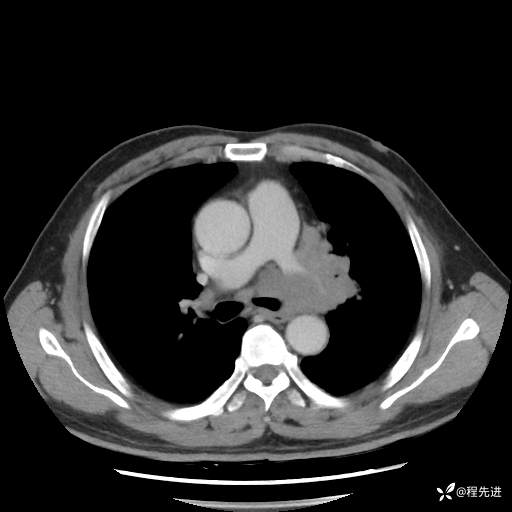

患者性别:男

患者年龄:57岁

简要病史:声嘶2月余

CT平扫+增强: